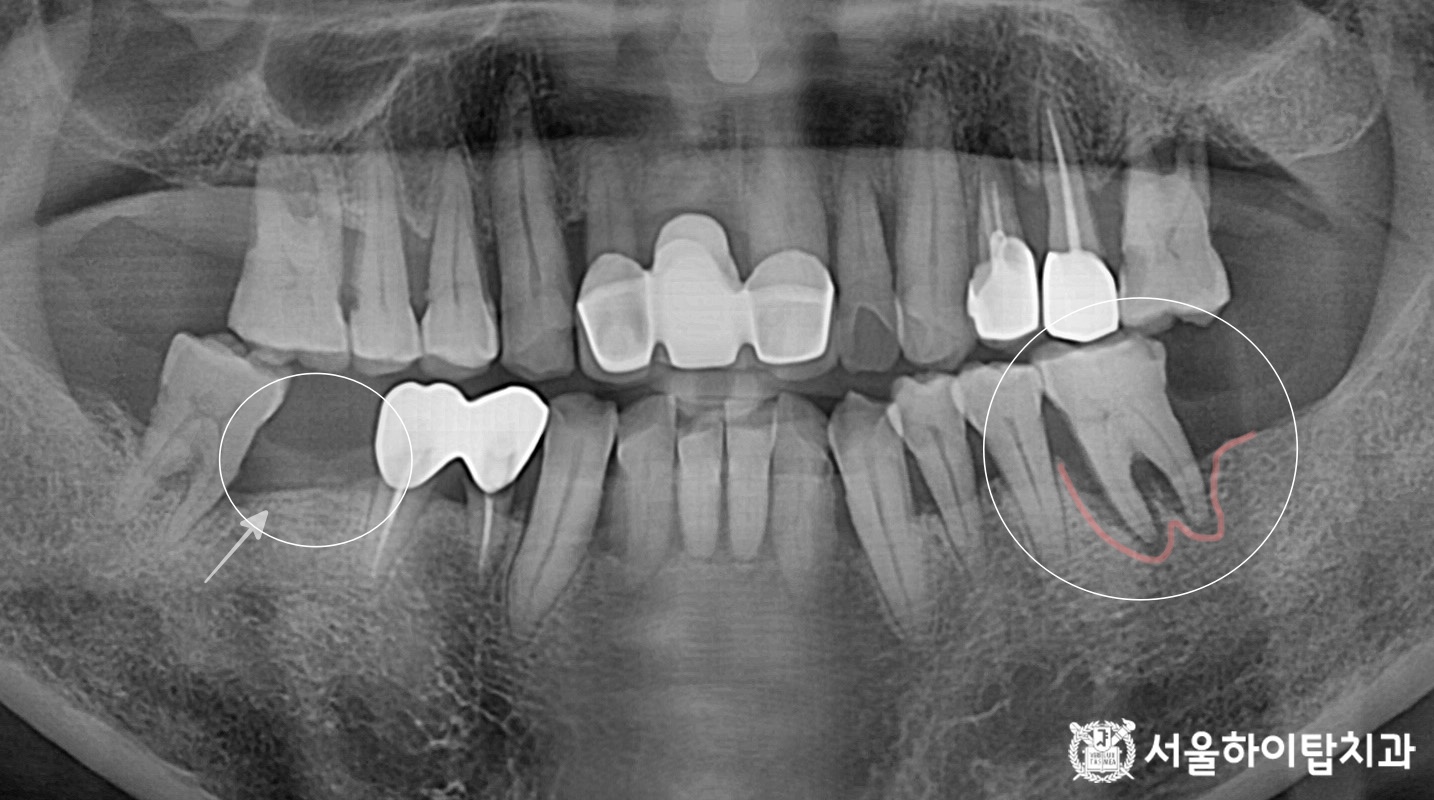

십정동 치과 어금니 상실 후 CT 기반 정밀 진단 후 진행한 당일 즉시 임플란트 진행 과정 동암역 치과, 불편한 앞니 바로 신경치료할까요? 검사부터 치료까지 (치근단 염증 · PFM 크라운) 주안역 치과 치아 흔들림(동요도 3도) 발치 후 임플란트 진행 과정 부평 치과 치아 머리·목 부분에 진행된 충치, 신경치료 과정 및 장기적 파절 가능성 안내 십정동 치과 앞니에서 파절이 쉽게 일어나는 부위가 있다? 절단연 파절 후 레진 수복 과정 간석오거리역 치과 치수까지 침범한 충치, 발치 후 임플란트 진행 과정 (정기검진과 조기 치료의 중요성) 만수동 치과 80대 고령환자, 심한 충치 치아 발치 후 임플란트 수술 과정 (발치가 필요한 충치?) 백운역 치과 신경치료 후 앞니 치아가 파절되기 쉬운 이유가 무엇일까? 임플란트 수술 과정 주안동 치과 70대 고령 환자│뿌리까지 이어진 치아 파절의 원인과 임플란트 수술 과정 간석동 치과│치주염으로 인한 골 흡수와 치아 흔들림, 뼈 이식을 동반한 임플란트 치료 과정 부평 치과 심한 치아 통증 엑스레이에서 보이지 않는 치수염? 신경치료와 크라운 수복 과정 만수동 치과|성장기 치아 상실, 왜 성인이 되어 임플란트를 했을까요? (상악동 거상술 동반) 십정동 치과 상실된 치아가 불러오는 연쇄적 문제? 치조골 흡수와 기울어진 어금니, 뼈이식 동반 임플란트 과정 동암역 치과 : 균형 잡힌 저작이 중요한 이유, 전반적으로 손상된 치아 및 잇몸 임플란트를 통해 저작 기능 개선 간석역 치과 치주염으로 인한 치조골 흡수, 치아 파절 및 마모까지 임플란트 가상 시뮬레이션을 통한 안전한 수술 과정 1 2 Next Archives 2026년 4월 2026년 3월 2026년 2월 2026년 1월 2025년 12월 2025년 11월 Categories 미분류 신경치료 심미 치료 임플란트 BACK TO TOP